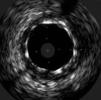

The procedure was performed by radial approach using a 7F guiding catheter. Plaque preparation was performed with rotational atherectomy using a 1.5 mm burr (Figure 3) and further predilation with a cutting balloon (3-3.5 mm). After balloon dilatation, rupture of severely calcified plaque was detected by IVUS (Eagle Eye; Volcano Corporation, Rancho Cordova, CA, USA), so we proceeded to implant a 3.5 mm×20 mm CRE 8 DES in the LM and LAD (Figures 4 and 5). At this point the wire was accidentally pulled back and was reintroduced into the LM and LAD. Post-dilatation was performed with a 4 mm non-compliant balloon. IVUS examination with manual pull-back at this stage revealed that the proximal part of the stent in the LM had been crushed as a result of lateral reintroduction of the wire through a proximal stent strut. The patient remained stable with normal flow in the LM and LAD. Guided by IVUS, a second wire (Sion, Asahi Intecc, Japan), with a 30° bend in its 1 mm distal tip, was introduced within the crushed stent segment (Figure 6). Once the guidewire was positioned inside the stent, progressive dilations with small (1.5 mm) to large (4 mm) balloons were performed until the stent regained its cylindrical shape (Figure 7). IVUS exploration detected an image suggesting dissection in the proximal end of the stent (Figure 8), and so a second DES (4 mm×8 mm Onyx) was implanted in the ostial-proximal segment of the LM, overlapping the previous stent (Figure 9), with an adequate angiographic final result (Figures 10 and 11). IVUS revealed correct stent expansion and apposition in the LM (Figure 12).

As the patient was stable, and taking advantage of the size of the 7F guiding catheter, we introduced a new guidewire under IVUS guidance within the lumen of the crushed stent segment. After step-by-step dilatation with smaller to larger balloons, the crushed stent segment regained its cylindrical shape. Although another practical solution would have been to implant a new stent (stent-in-stent), we chose the former strategy and consequently avoided the placement of multiple layers in the proximal segment of the LM. Finally, the implantation of a second stent, overlapping with the proximal end of the previous stent in the LM, enabled the coverage of both the proximal end dissection and the proximal part of the reconstructed stent segment. Considering that in the latter part the struts appeared to be incomplete in some circumferential points (Figure 7), the implantation of a new stent could remedy this defect.